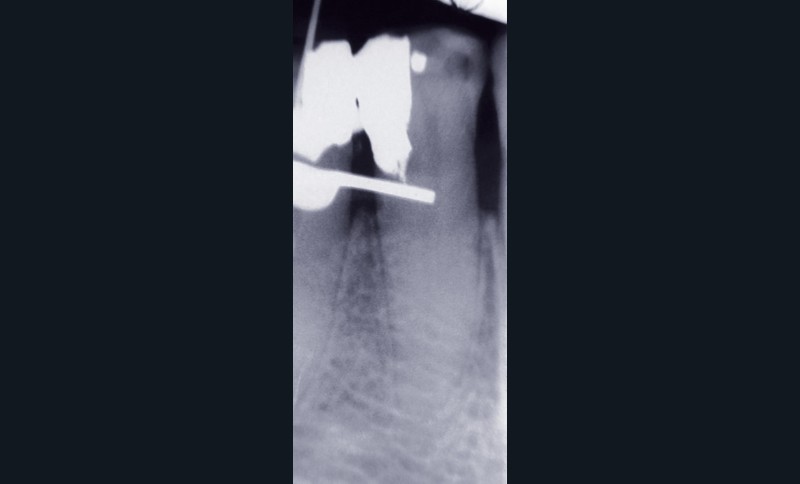

Madame RR, âgée de 67 ans, en bonne santé générale, nous consulte pour une gêne importante lors de la mastication, qu’elle situe au niveau de la première prémolaire mandibulaire droite. L’historique du cas révèle que cette dent avait été traitée en première intention voici quatorze ans par nous-mêmes pour des raisons prothétiques (pulpectomie prothétique) (fig. 2 et 3).